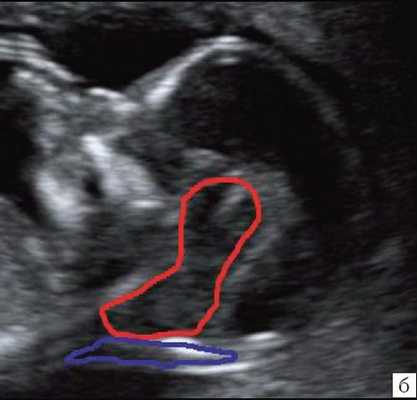

На продольных срезах позвоночника на уровне Th 11 - L3 определяется дефект позвоночника (Указан пунктиром) (Согласна, что она еле заметна, но учтите, что срок беременности еще всего 13 нед!)

Хорошо определяется изгиб в виде "горба" ниже дефекта, в поясничном отделе позвоночника. Пунктирной линией показан ход позвоночного столба.